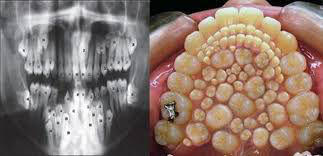

でも強そうやな

便利やんけ!

隙間にクッソはさまりそう

ストレスで死にそう